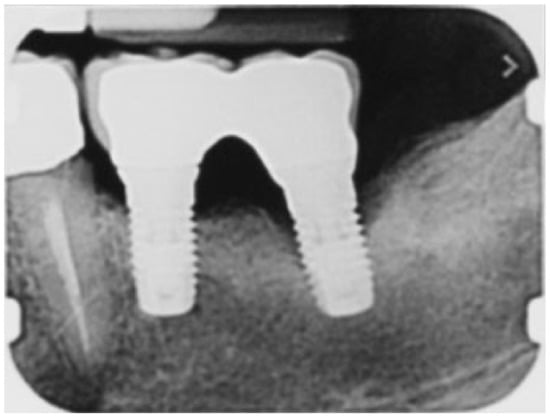

During open-flap debridement of the infected implant surface with sodium bicarbonate air powder abrasion (PROPHYflex™ 3 with periotip, KaVo, Biberach, Germany) (Figure 3), rapid onset swelling arose on the left cheek as well as in the periorbital space. The procedure was stopped immediately and the surgical area was rinsed with sterile saline solution to remove all residual bicarbonate particles. Before repositioning and suturing the flap, intra- and extra-oral inspection and palpation of the face and neck were performed to determine the spread and extension of entrapped air. Extra-oral examination revealed slight asymmetry of the face and complete left eyelid ptosis due to swelling of the left periorbital space and cheek (Figure 4).

Figure 3. Intraoral image during open-flap air-powder abrasive debridement of the infected implant surface.